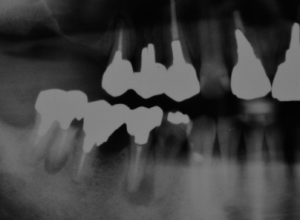

初診時のレントゲン写真。

治療後2年経過。根の先の黒い影が消えています。